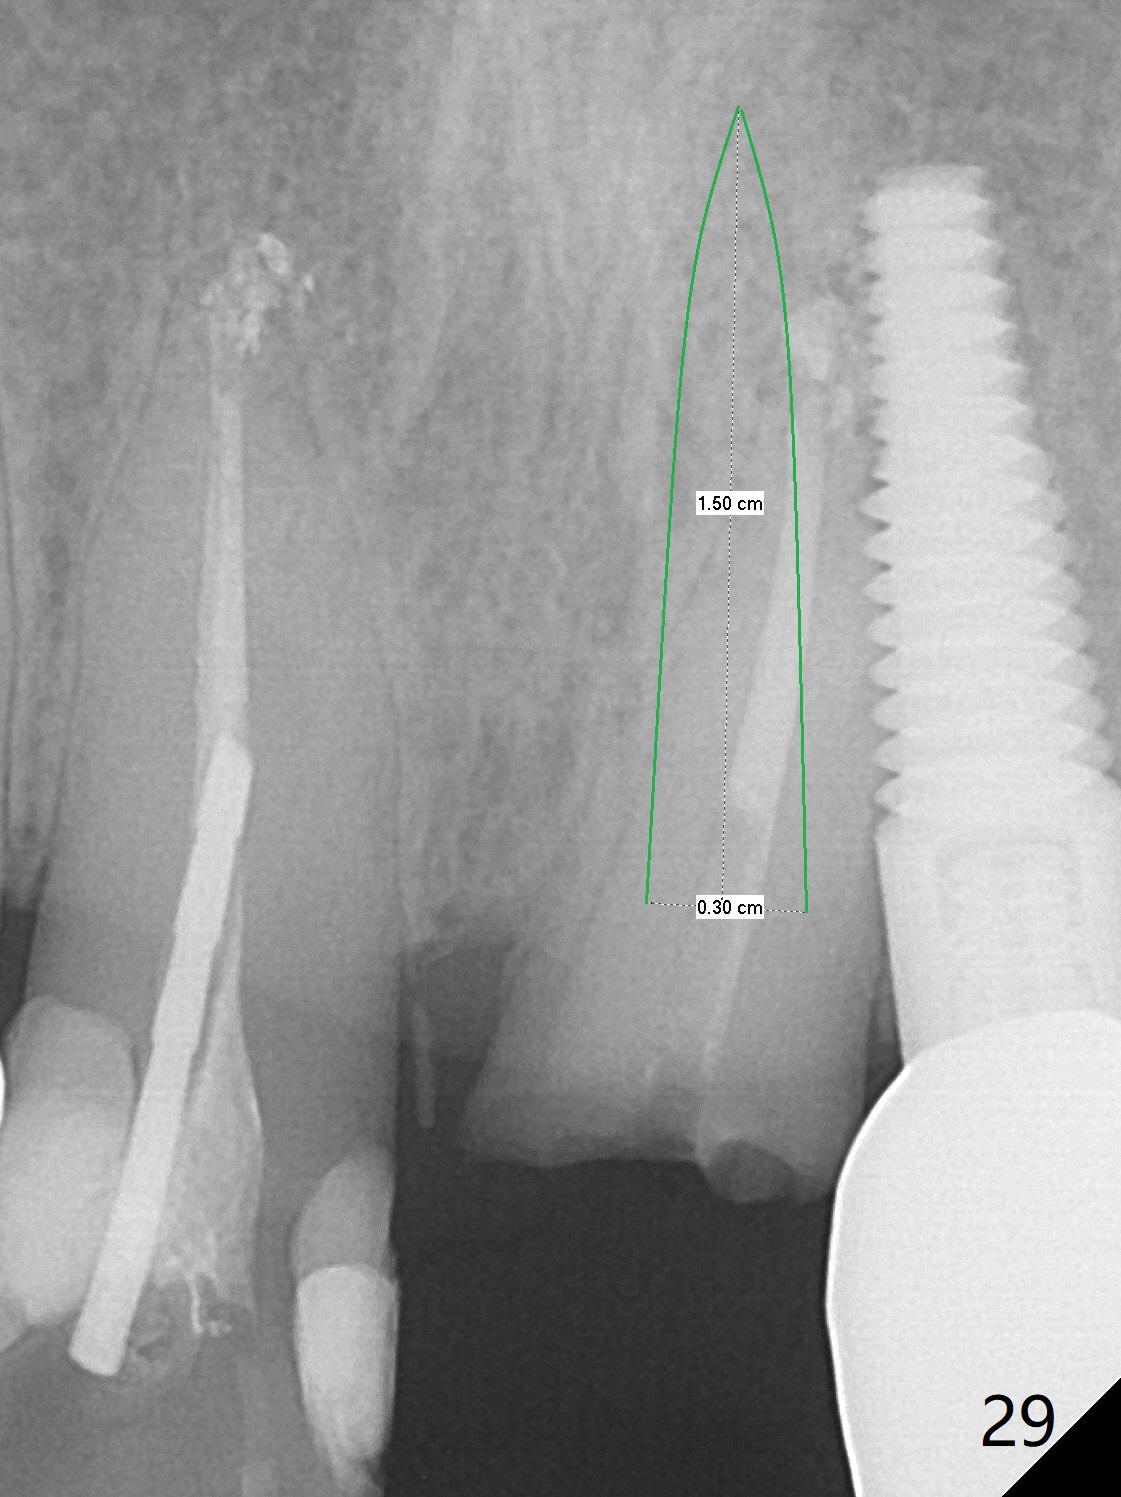

Six months post cementation, the tooth #9 becomes symptomatic. Is it possible that the implant at #10 is too close to the root of #9? It is asymptomatic after pulpotomy, but the tooth fractures equi/supragingivally. Two PAs taken while RCT show osteointegration at #10-12 (Fig.18,19). While the bone density increases at #10 regular implant, there is minimal bone loss around the 1-piece implants 13 months post cementation (18 months postop, Fig.20,21). The gingiva remains healthy 19 months post cementation (Fig.22). 76岁病人突然打电话说一个植牙牙冠松动,其实9号牙(自然牙)折裂,6,10-13号牙植牙好像没有骨质吸收(图二十三至二十五),10-13牙位牙龈健康(图二十六,行使功能五年)。9号牙牙冠重新粘固后,显示前牙深覆合,深覆盖(图二十七,二十八)。如果再次脱落需要植牙,选择一段式有助于植入和修复,因为植体和基台直径小。两段式植牙相对基台直径至少4,或者4.5毫米,前牙修复显得笨重。由于9,10牙根和植体接近,9号牙植体需要偏小而长,3x14或者15毫米(图二十九)。